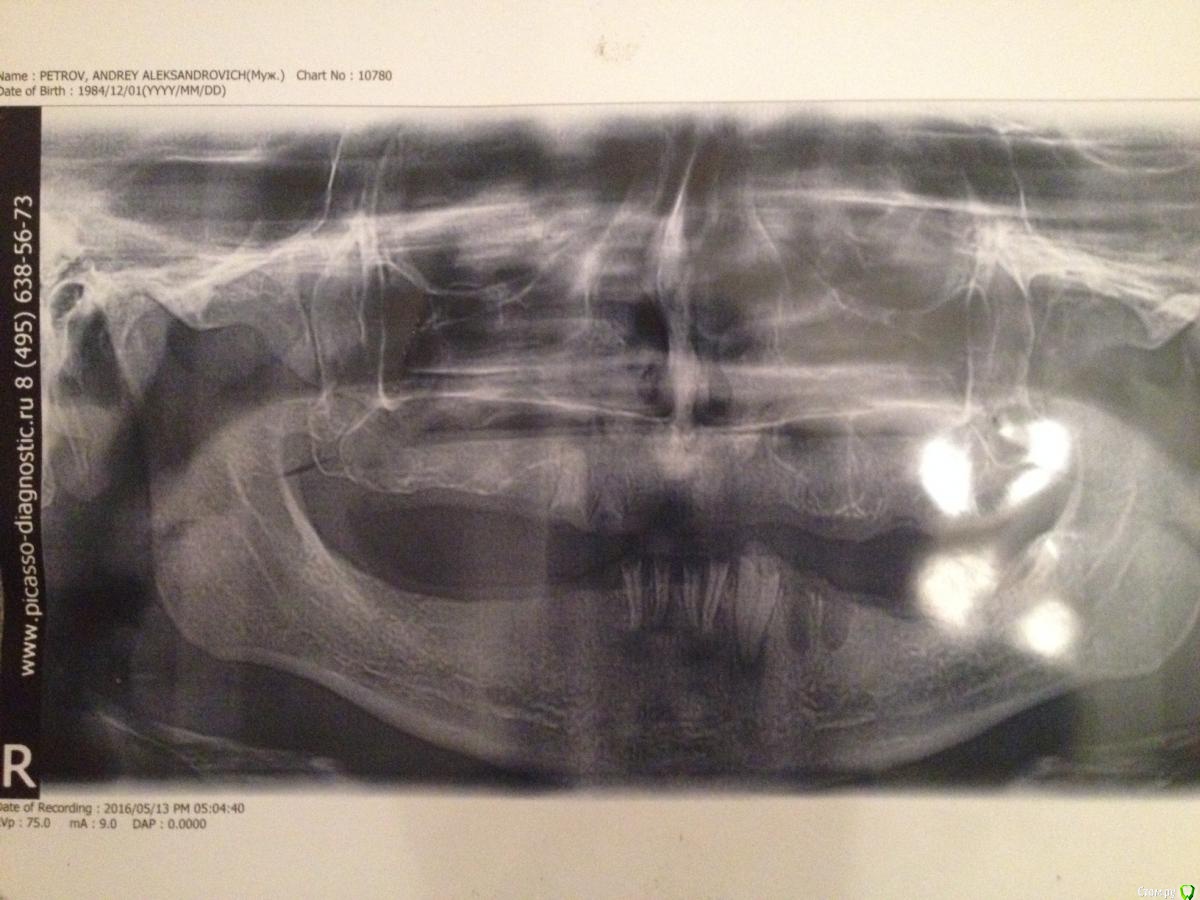

apetrov84 Опубликовано 22 мая, 2016 Поделиться Опубликовано 22 мая, 2016 Здравствуйте.Позавчера удалял последние зубы снизу. В меня вкололи тонну обезболивающего, так как сохранялась сильная чувствительность. После удаления хирург сказал, что была киста. Сейчас сохраняется боль в области удаления, но она не острая. Может ли киста после удаления появиться снова? и может ли ее удаление повлиять на скорость заживления? Перед удалением я делал снимок. но доктор ничего про кисту не сказал. Видно ли ее на снимке вообще? и нет ли кист в других местах? Ссылка на комментарий

red_butler Опубликовано 22 мая, 2016 Поделиться Опубликовано 22 мая, 2016 Кисты нет, был периодонтит. Причина устранена (инфицированные корни) и воспаление теперь пройдет. 1 Ссылка на комментарий